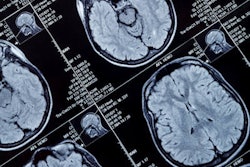

At the second session, participants underwent resting-state, 3-tesla fMRI (Skyra, Siemens Healthineers) before the start of the same ethanol-saline concoction to gather baseline data. As the infusion proceeded, the researchers acquired timely whole-brain structural and diffusion-weighted MR images, along with a second resting-state fMRI scan at the target alcohol level.

MR brain images show the effects of drinking in the past 30 days, with excessive alcohol changing connectivity in basil ganglia region. Increases in connectivity from intoxication are indicated in red, while connectivity decreases are in blue. Images courtesy of PLOS One.As one might expect, fMRI scans showed that increased alcohol intake correlated with greatly reduced connectivity in the globus pallidus externus, particularly to the striatum, which is involved in cognition and decision-making. As a result, subjects with impulsive behavioral traits who overly imbibed alcohol were "particularly vulnerable" to their brain's inability to signal that it is time to stop drinking and avoid intoxication.